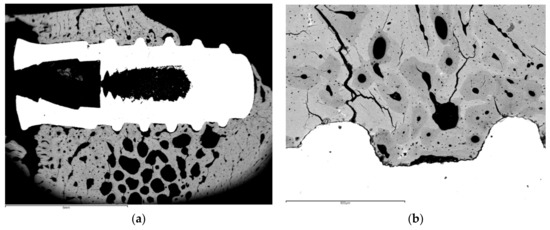

Klockner’s dental implantations were performed on pigs at different times of osseointegration. In Figure 11, the thermochemical treatment (2S) can be observed, showing that the sodium titanate had a good osseointegration at 4 weeks after implantation. This value is compared with other surface treatments (R: roughened by blasting; E: acid attack; Ctr: control). These values show an acceleration of bone in-growth around the dental implant, which was already significant 2 weeks after implant placement. These implants provided excellent primary fixation, even before the hard tissues started to significantly regenerate. These osseointegration levels evidenced the good short-term in vivo performance of the treated surfaces in comparison with the other conventional implants tested. Osseointegration was accelerated and, consequently, implant failure decreased. Figure 12 indicates the osteoconductive behavior of the thermochemically treated surface two2-step), where it can be observed that the new bone is growing from the surface of the implant [44,45,46].

The histologies show how the implant surface facilitates the formation of bone, as shown in Figure 12 and Figure 13, and where bone is formed from the implant surface with sodium titanate. With this, an osteoinductive effect is achieved that favors the reduction in osseointegration time [47,48,49,50].

Figure 13. Histology at 2 weeks after implantation. (a). Dental implant with an osseointegration of approximately 70% after two weeks of implantation. (b). At higher magnification showing the implant-bone tissue interface.